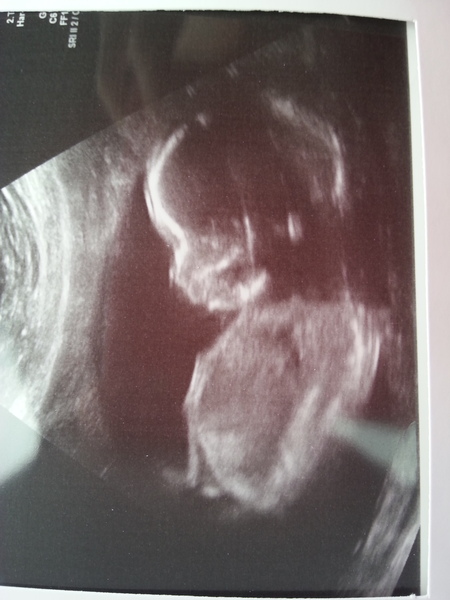

21 weeks today and baby behaved really well for the scan. everything was as it should be and no problems! so relieved and excited!

hospital messed up the appointment (had cancelled it without telling us! ) but got it sorted and have us the scan pics for few to apologise! Here is baby anyway!

Great news Cheshire. Lovely photo!

Wow cheshire you're super organised!! Lovely scan picture Smile

Beautiful scan pic chesire :)